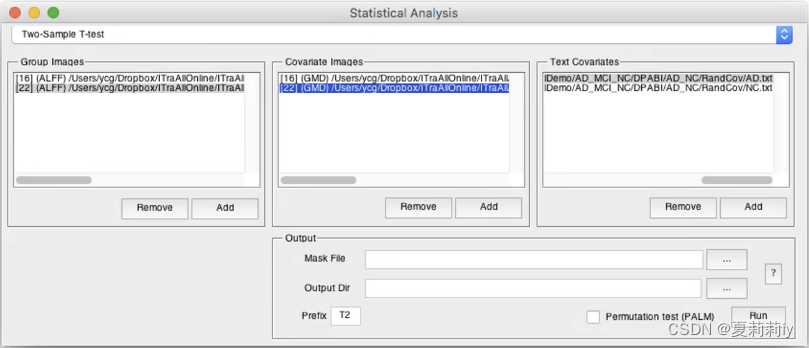

(4)Two-Sample T-Test

①One Sample是没有实际意义的,一般要使用Two-Sample来进行数据分析

②在左方添加两个文件夹(值第一组减去第二组的值,所以顺序很有关系)

③上图中Covariate Images添加的灰质密度图像,Covariate Images为图像协变量

④功能上一般是3*3*3的voxel size,但结构上一般是1*1*1或1.5*1.5*1.5。此时用Utilities→Image Reslicer可以将结构像变成功能像的大小,否则在这不一样大会报错

⑤上图中Text Covariates添加了头动,Text Covariates是文本协变量